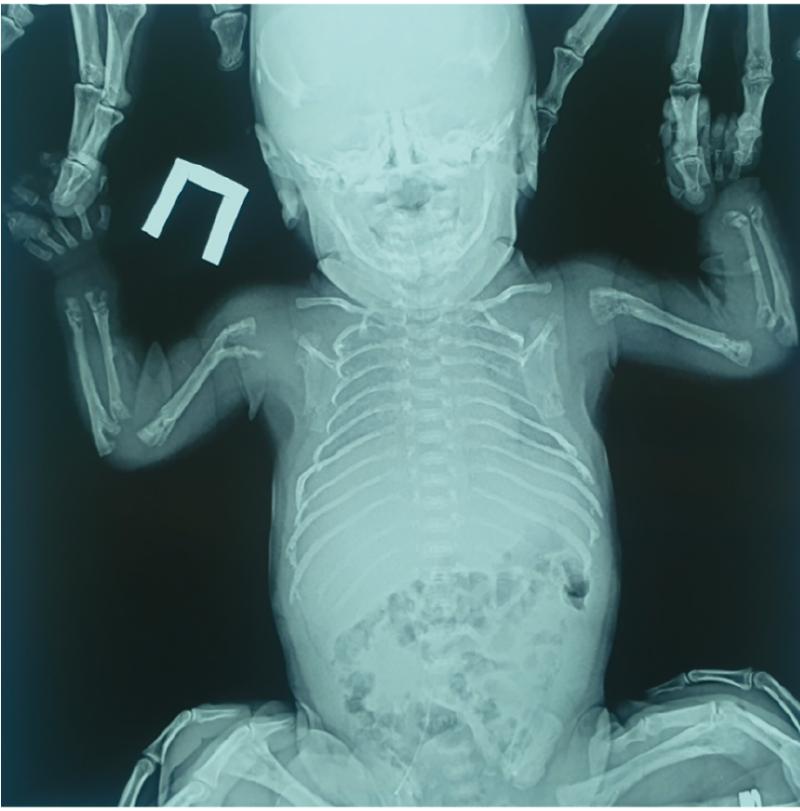

- Рентгенография. Это ключевой метод диагностики. Рентгеновский снимок кисти в прямой проекции позволяет детально рассмотреть кости пальцев, подтвердить наличие аномальной трапециевидной или треугольной средней фаланги и точно измерить угол деформации.